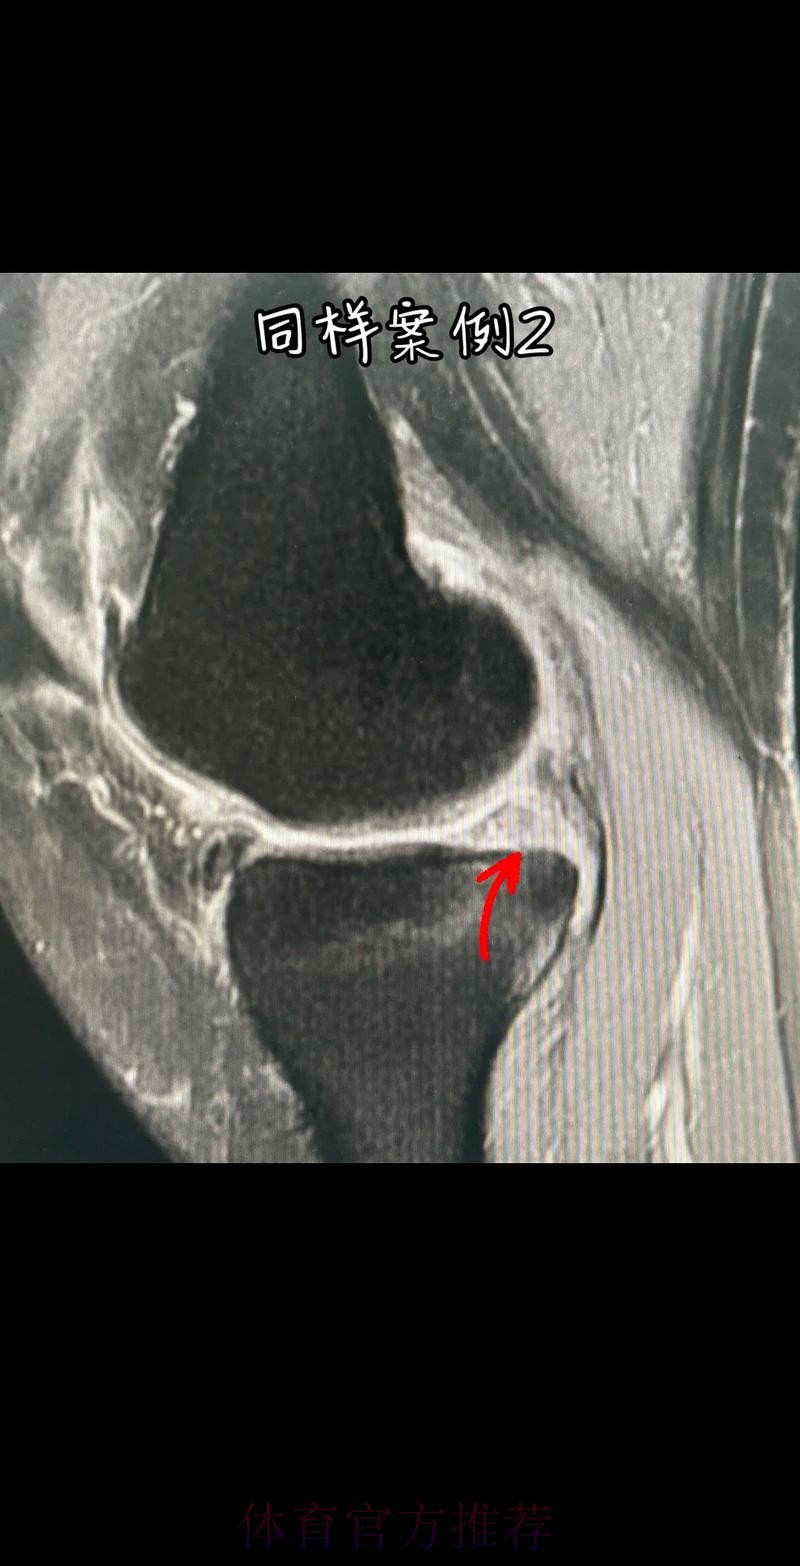

官方:阿拉巴左膝内侧半月板撕裂 预计伤缺6-8周

这条“官方 阿拉巴左膝内侧半月板撕裂 预计伤缺6-8周”的声明一出 不只是伤病通告那么简单 它背后牵动的是皇马后防体系的重塑 奥地利国家队备战计划的调整 以及一名顶级后卫职业生涯中一次关键的健康考验 对于已经习惯在高强度赛程中同时承担俱乐部与国家队重任的阿拉巴来说 这次伤病既是一次身体的警报 也是一次心理与战术层面的巨大挑战

在现代足球中 像阿拉巴这样能胜任中卫 左后卫 甚至后腰的多面手几乎是教练心中最理想的拼图 他不仅是后场的防守屏障 更是从后场发起进攻的节拍器 因此 当“左膝内侧半月板撕裂 伤缺6-8周”这样的诊断从官方口中给出时 对球队来说 就等同于在关键路段突然失去一块核心路基 球迷最直观的担忧是 皇马在这段时间是否还能保持防线稳定 奥地利是否在国际比赛日期间陷入被动 而对阿拉巴本人而言 这则官方消息意味着一个不得不按下暂停键的阶段 他需要重新面对恢复训练 康复计划 以及未来的竞技状态

阿拉巴在皇马的定位从来不只是“中后卫”这么简单 他可以在三中卫体系中担任左中卫 也可以在四后卫体系中出现在左后卫甚至拖后组织者的位置 在很多场次中 他会频繁前插 参与推进和组织 这意味着他在身体对抗 启动速度 横向移动和急停变向上的负荷都极高 半月板本身就处在运动生物力学的核心位置 当一名球员同时承担高强度防守和大量持球推进任务时 半月板承受的剪切力和压缩力都会显著增加 这也是为什么像阿拉巴这样“全能型”球员 更容易在高密度赛程中出现膝关节相关损伤

从医学角度看 半月板是膝关节内一块呈“C”形的软骨结构 其作用是缓冲冲击 稳定膝关节 并帮助分散压力 “左膝内侧半月板撕裂”通常说明在一次急停 旋转 或对抗中 半月板受到了超过其承受极限的力导致结构损伤 这类伤病常见于足球 篮球等需要频繁变向和对抗的项目 对于职业球员而言 半月板损伤严重程度不一 但共同点是都会影响支撑发力 跳跃以及变向时的稳定性 而官方给出的“预计伤缺6-8周”这个时间区间 往往对应的是中度损伤或通过微创手术加积极康复能够较快回归的情况 也意味着暂时没有出现必须长时间休战的最坏结果

表面上看 6-8周只是一个时间区间 但对顶级球队的赛程来说 这段时间可能包含多场联赛 甚至关键杯赛淘汰轮 相当于缺席一个赛季中最密集的一段周期 需要强调的是 这个“预计”并不是绝对数字 它取决于撕裂的位置 大小 修复方式 以及球员个体的恢复能力 有时若采取保守治疗 球员在6周时即可参与部分训练 但要达到比赛要求则可能接近8周甚至稍长 此外 精英运动员的康复不仅仅是伤口愈合 还包括力量恢复 协调重建 和心理自信的回归 阿拉巴要在有限时间内完成从“伤病患者”到“可靠首发”的角色转换 这一过程复杂程度远远超出一纸通告所能呈现